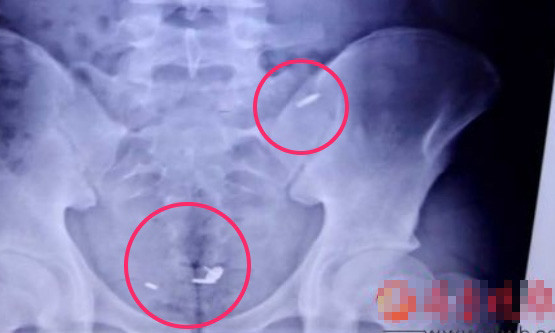

Phim chụp X-quang khoang bụng thiếu niên Wang.

Hôm 7/7, một nam sinh 16 tuổi, được xác định là Wang Chuan, cá cược với bạn cùng lớp sẽ nuốt chiếc đinh bấm để đổi lại khoản tiền 200 nhân dân tệ. Không chỉ vậy, thiếu niên này còn nhét ba ngòi bút bị vào bụng thông qua lỗ rốn.

Bên cạnh đó, ekip điều trị phải trải qua 4 giờ định vị và loại bỏ từng ngòi bút bi dài tầm 1 cm bằng ống nội soi. Được biết, công việc này khá khó khăn vì ngòi bút liên tục thay đổi vị trí.